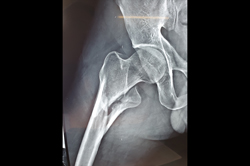

Intertrochanteric Fracture